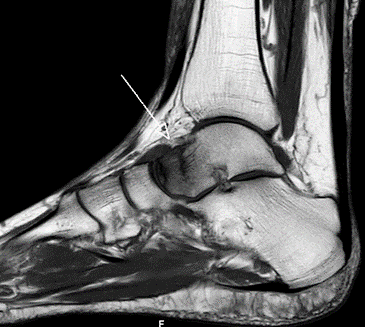

Die Röntgenuntersuchung ergab keinen pathologischen Befund. (Abb.1 und 2)

Abb.1 Unfallbild a.p.